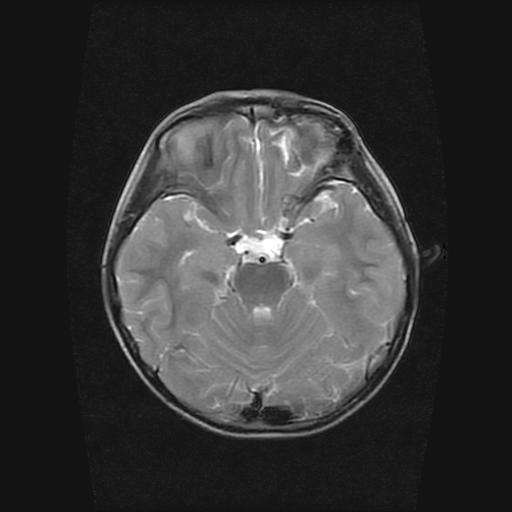

标题: PED0377: 6岁小儿,左侧视神经瘤术后

6岁小儿,左侧视神经瘤术后。现左侧视力减退。